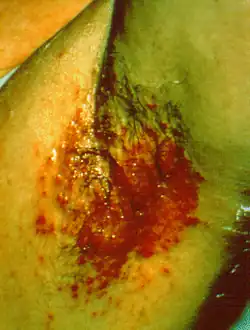

Intertrigo

| Axillary intertrigo (bacterial) | |

Intertrigo, commonly called "skin fold dermatitis", refers to a type of inflammatory rash (dermatitis) of the superficial skin that occurs within a person's body folds.[1] These areas are more susceptible to irritation and subsequent infection due to factors that promote skin breakdown such as moisture, friction, and exposure to bodily secretions and excreta such as sweat, urine, or feces.[2] Areas of the body which are more likely to be affected by intertrigo include the inframammary fold, intergluteal cleft, armpits, and spaces between the fingers or toes. Skin affected by intertrigo is more prone to infection than intact skin.[2]

The term "intertrigo" commonly refers to a secondary infection with bacteria (such as Corynebacterium minutissimum), fungi (such as Candida albicans), or viruses. A frequent manifestation is candidal intertrigo.